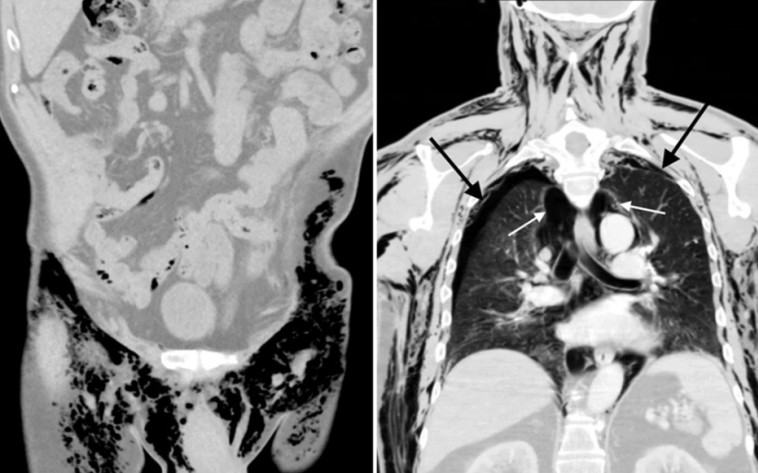

לפי הדו"ח הרפואי, אם לא היה מקבל טיפול בזמן, הדבר היה עלול לפגוע לצמיתות בתפקוד הלב והריאות של האיש, פרט שיכול היה להוביל למוות. מאוחר יותר, התגלה שהמקור העיקרי לשריקות המוזרות מאשכיו של האיש, היה פצע פתוח בצד שמאל של השק. הפציעה נגרמה בעקבות ניתוח אשכים שעבר האיש כחמישה חודשים קודם לכן, כדי להפחית נפיחות ממנה סבל ולאפשר לאוויר שהיה כלוא בגופו לצאת החוצה.

התופעה נקראת pneumoscrotum. זהו מצב נדיר שבו אוויר נלכד בשק האשכים ובספרות הרפואית תוארו 60 מקרים בלבד עד היום. מכיוון שהאוויר לא יכול לצאת החוצה באופן טבעי דרך פתחי הגוף, המקרה דורש בדרך כלל התערבות רפואית. האלמוני סבל מהתופעה במשך שנתיים שתוארו כ"זמן ארוך באופן חריג".

קוצר הנשימה ופניו הנפוחות נבעו מסיבוכים שונים, כך נכתב בדו"ח. שני צינורות הוכנסו לחזה של האלמוני כדי לנקז עודפי אוויר. ריאותיו התאוששו לאחר שלושה ימים בבית החולים והוא שוחרר במצב טוב.